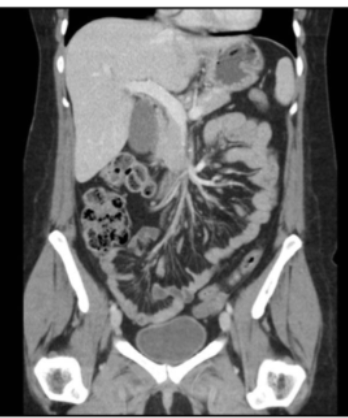

13

Q

what type of window

A

lung

14

What are all the windows

BLM BSA:

Bone

mediastinum

brain

soft tissue

abdomen

Windowing = grey-level mapping contrast enhancement

- adjusts the display settings of the CT images to emphasize specific types of tissue, making it easier to diagnose various conditions